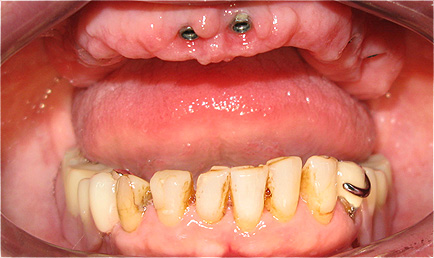

Caso 3 - Desdentado total reabilitado com prótese acrílica removível inferior, barra e clips para retenção e estabilidade

![]() |

![]() ![]() |